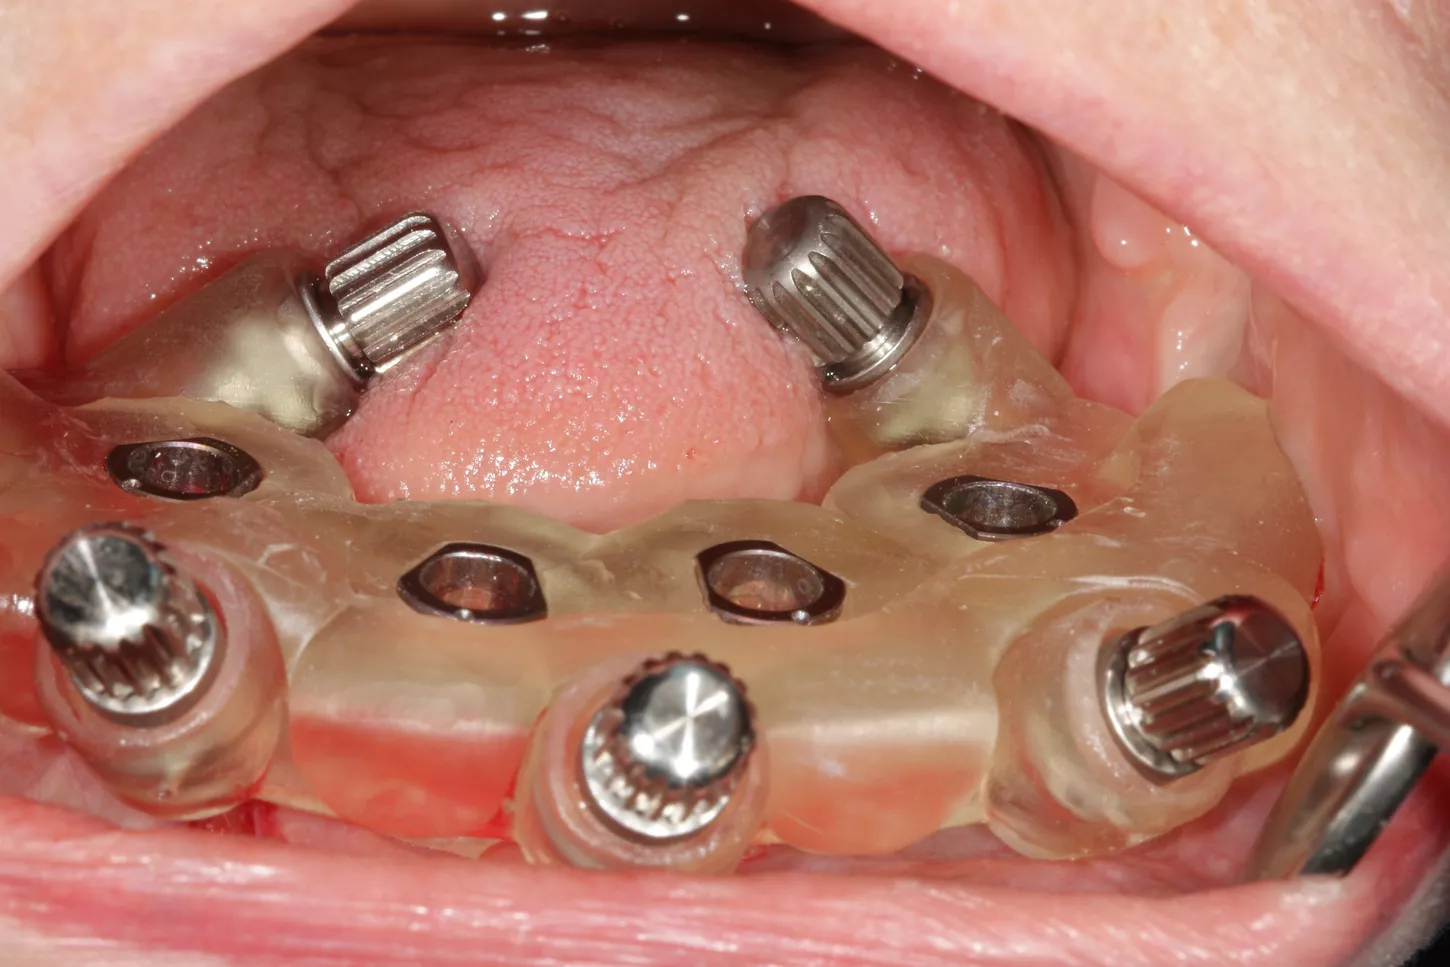

14. Positioning of the transfers in the lower jaw for impression.

15. The framework structure for the lower jaw ensures a precise fit on the 4 Axiom X3® TL implants.